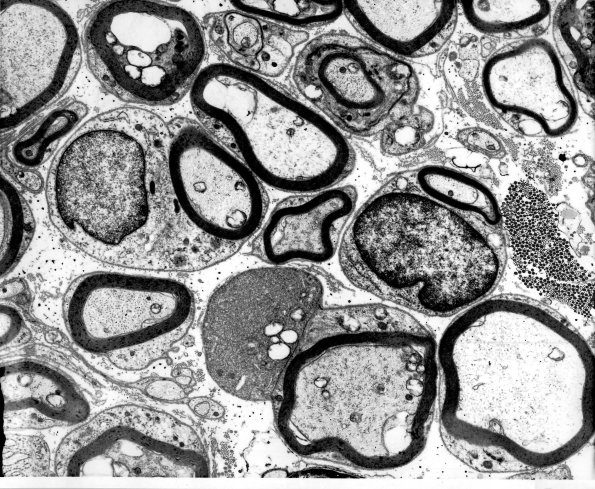

12A1,2 Occasionally a mature axon may be paired with a dystrophic axon (arrow, 12A2), support for the idea that the frustrated regenerating axon has not been completely pruned and lost. (electron micrographs)